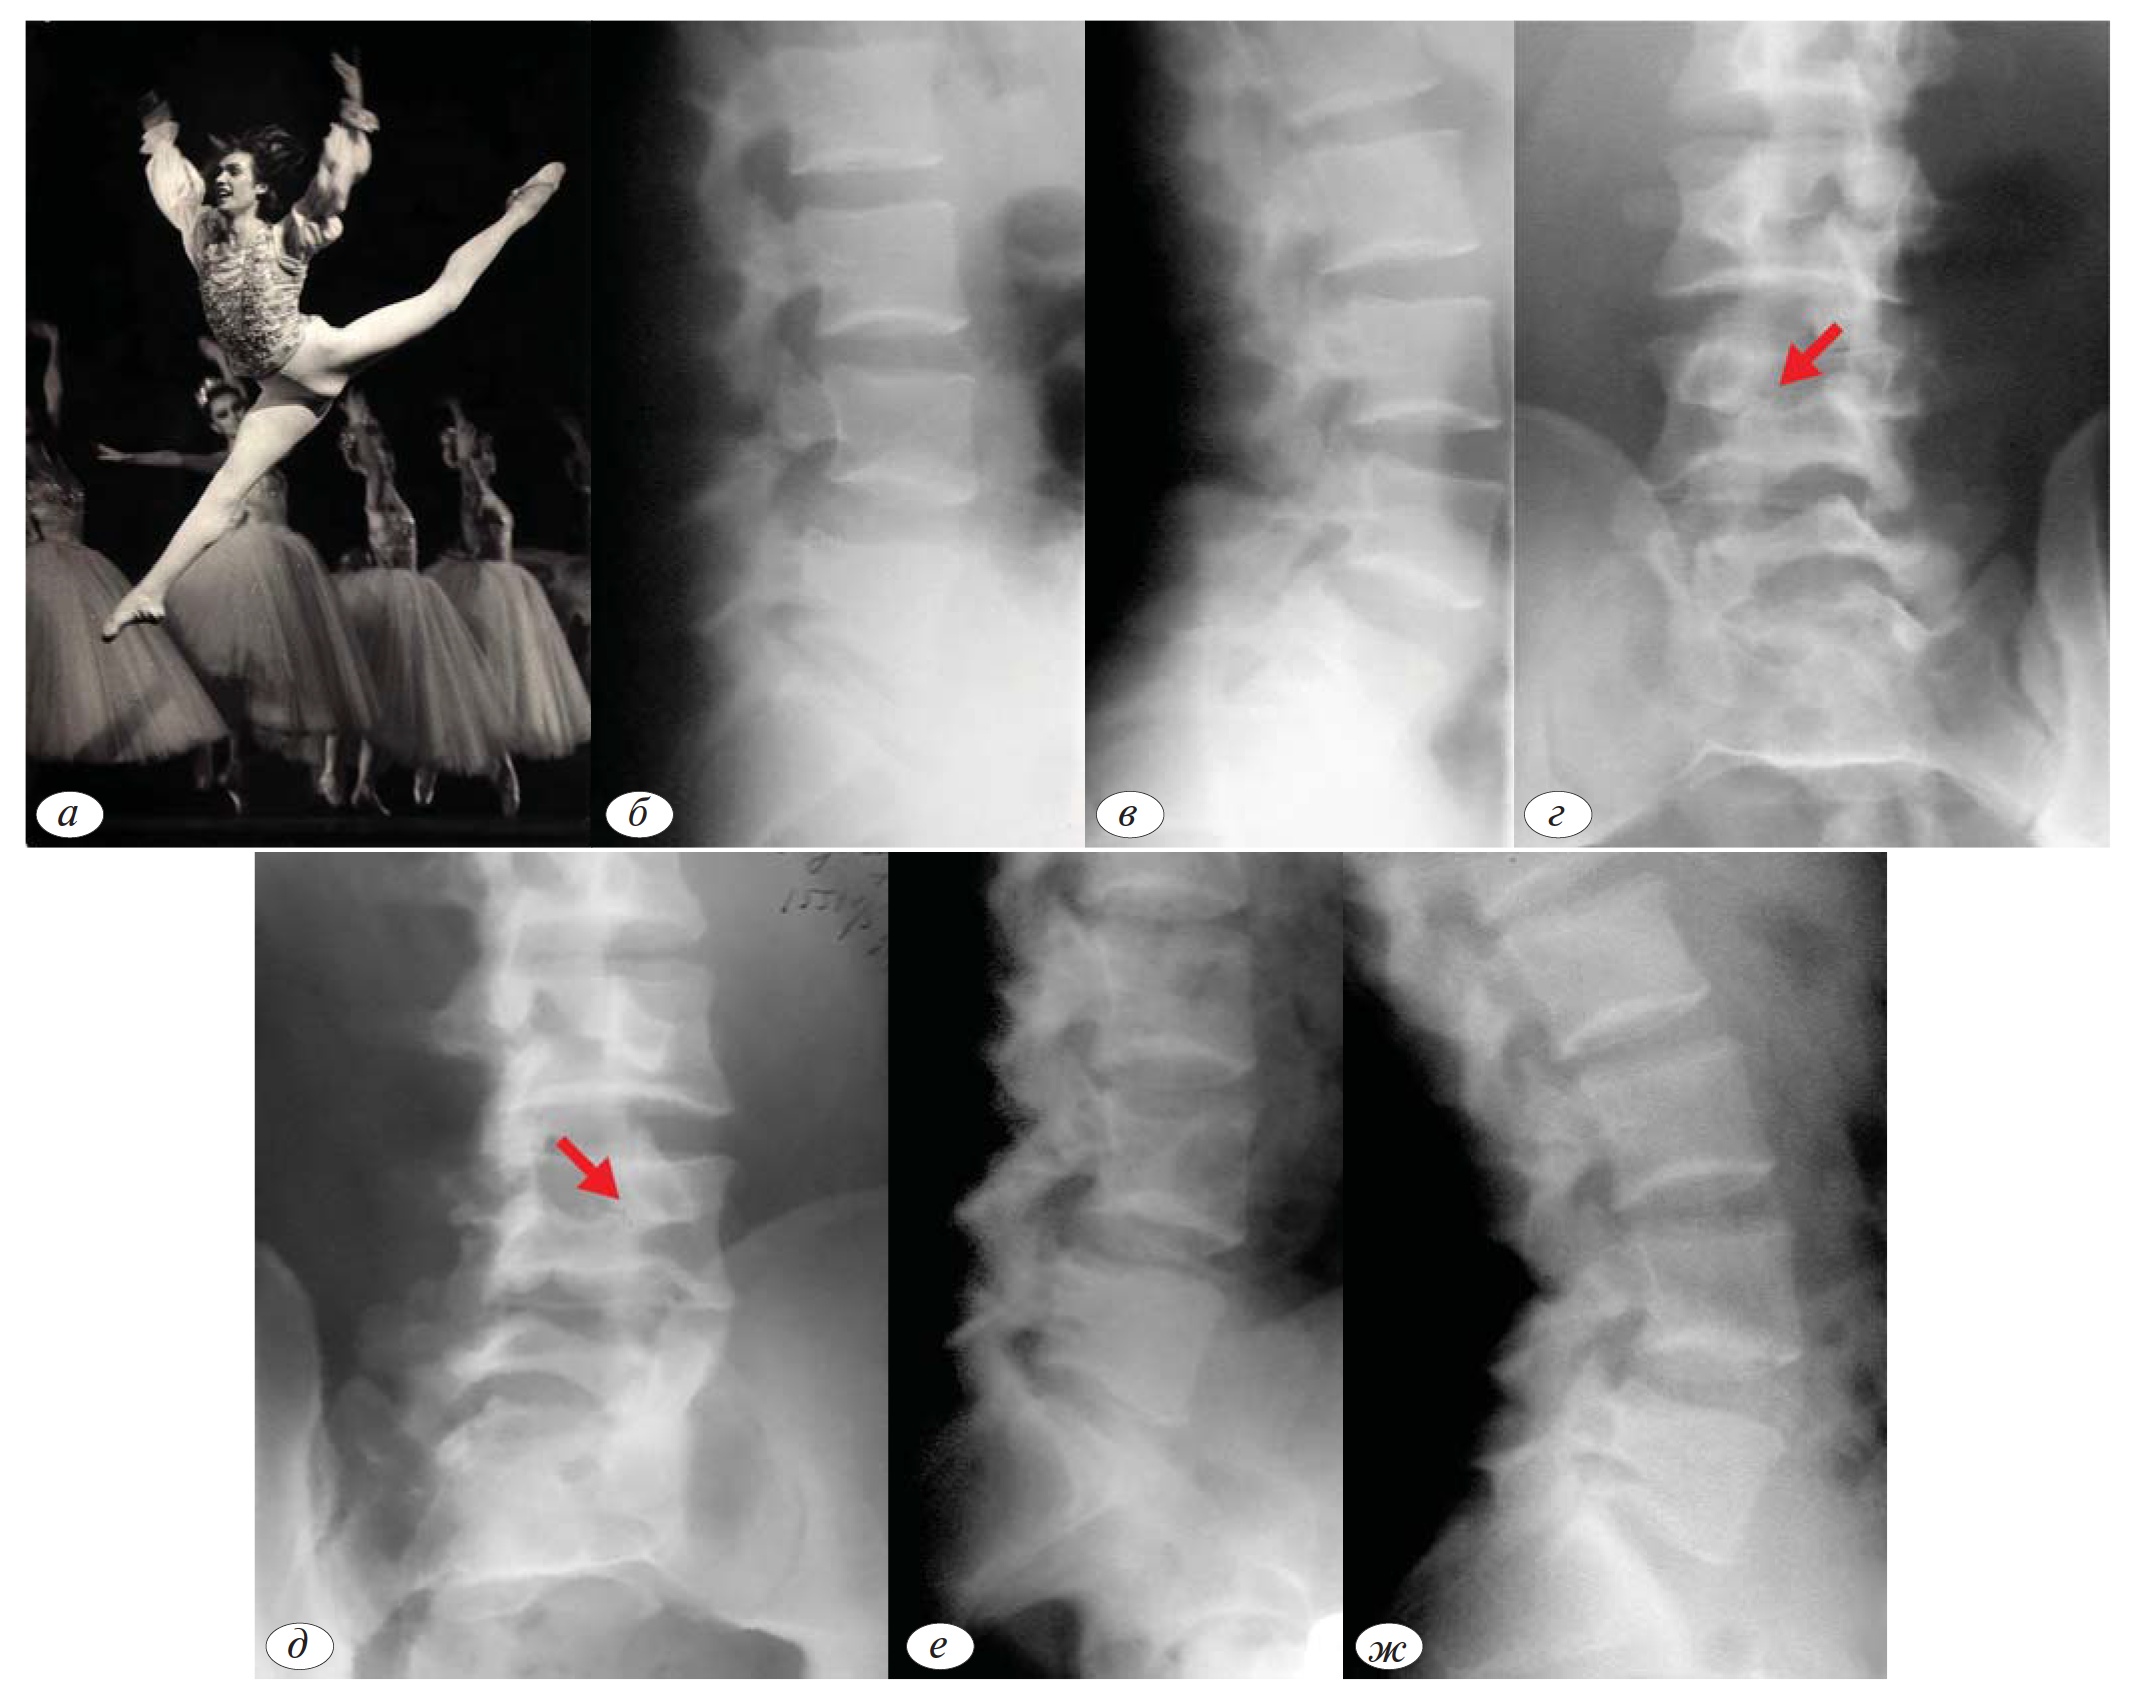

Пациент Н., ЗМС, многократный чемпион мира и Олимпийских Игр по спортивной гимнастике, член Сборной России. В возрасте 16 лет впервые обратился в клинику спортивной и балетной травмы ЦИТО по поводу пояснично-крестцового болевого

синдрома. Тогда был диагностирован острый спондилолиз L5 позвонка (рис. 2, а—в), проведен курс консервативного лечения. К тренировкам был допущен через 3 мес. В последующем отмечал иногда незначительные боли в поясничном отделе позвоночника при выполнении акробатических элементов. Через 4 года повторная госпитализация в ЦИТО в связи со значительным обострением болевого синдрома. Рентгенологически определялось формирование ложного сустава в области дужки L5 позвонка, спондилолистез L5 с явлениями нестабильности (рис. 2, г—е). Облегчение после курса консервативного лечения. При последнем обследовании через 10 лет со дня первичного обращения. на рентгенограммах отмечается прежняя степень смещения L5 позвонка, но без явлений нестабильности (рис. 2, ж—и). В настоящее время оставил соревновательную деятельность в связи с возрастом.

Рис. 2. Больной Н., ЗМС, спортивная гимнастика, сборная России.Рентгенограммы при первичном обращении в возрасте 16 лет — острый спондилолиз L5 позвонка (а), незначительная нестабильность L5-S1 при ФРИ (б, в); г — формирование ложного сустава в области дужки L5 позвонка через 4 года после первичного обращения; д, е — ФРИ — нестабильность L5-S1, антелистез L5; з, и — рентгенограммы через 10 лет после первичного обращения в возрасте 26 лет — ложный сустав дужки L5 позвонка (ж, стабилизация сегмента L5-S1.